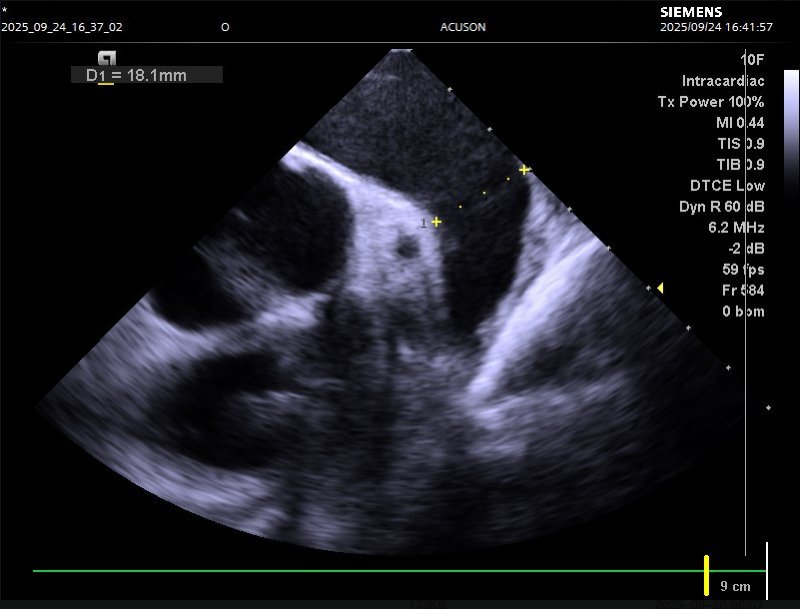

针对这一复杂病情,心血管内科系主任姜大明带领心律失常介入团队迅速开展多学科会诊。为确保手术安全与精准性,团队特邀李阳教授共同制定方案,并联合超声科1、CT科、麻醉科1等多科室提前做好术前准备:何昊医生与陈银凤医生通过食道超声检查,精准测量患者左心耳开口大小与形态,排除血栓隐患;CT科单世馨主任、马福成医生完成左心耳CT三维重建,清晰呈现解剖结构,为封堵器选型与手术路径规划提供“导航支持”。

食道超声及肺静脉CTV清晰呈现左心耳解剖结构

9月24日,手术在导管室正式开展。在麻醉医生王敏的全程保障下,手术团队借助心腔内超声(ICE)实时引导,仅用三小时便顺利完成两项关键操作:先是通过射频消融术,将导管经外周血管送入心脏,释放射频电流消融异常电信号传导路径,帮助心脏恢复正常节律;随后又通过左心耳封堵术,将封堵器精准送入左心耳并固定,隔绝血栓形成“温床”,从根源降低脑栓塞风险。